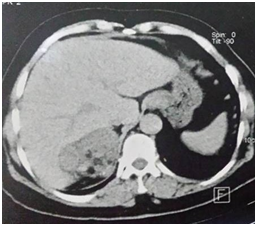

A CT scan showed a right lesional adrenal process, well confined by lobulated contours, hypodense, containing greasy spots and calcifications (Figure 1), heterogeneously enhanced after a contrastive injection (Figure 2), measuring 71×60×55mm.

Figure 2 Scanner showing adrenal mass heterogeneously enhaced after contrast injection and containing calcifications.

Frontwards, this process comes in contact with the inferior vena cava and segment VII of the liver without signs of invasion. Internally, he contacts the diaphragm’s pillar with the loss of separation greasy edges in some place. The radiological aspect is highly suggestive of malignant adrenal tumor.